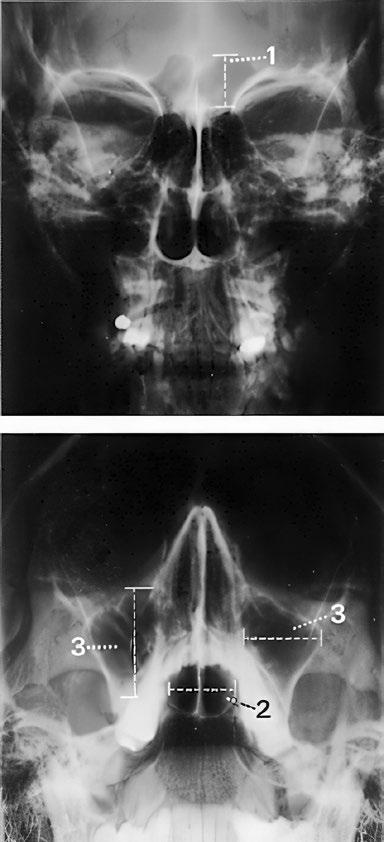

Paranazální dutiny

Paranazální dutiny a nosní dutina s uprostřed umístěnou nosní přepážkou jsou normálně vytvořeny a symetricky uloženy Vykazují normální pneumatizaci a transparenci vůči záření Kontury jsou hladké a ostře ohraničené Současně zobrazený skelet lebky je nenápadný Bez rentgenologicky patrných cizích těles

Závěr

Normální zobrazení dutiny nosní a paranazálních dutin

Kontrolní seznam

Tvar, velikost – dutina čelní (viz níže) – etmoidální sklípky – dutina kosti klínové – dutina čelistní (viz níže) – dutina nosní: symetrie, nosní přepážka uložena uprostřed

Pneumatizace – transparence záření (až na dutinu čelní stranově stejná) – bez zastínění – bez hladinek

Kontury – ostré, hladké – bez přerušení kontinuity – bez ohraničených ztenčení nebo ztluštění kortikalis – bez zduření

Ostatní skelet – obličejová část lebky, očnice a horní hrany pyramid: – tvar (symetrie) – struktura – kontury (linie projasnění)

Měkké tkáně – bez cizích těles nebo kalcifikací – bez otoku

Důležité rozměry

(1) Dutina čelní: výška asi 1,5–2,0 cm

(2) Dutina kosti klínové: šířka 0,9–1,4 cm

(3) Dutiny čelistní: výška a šířka asi 2 cm